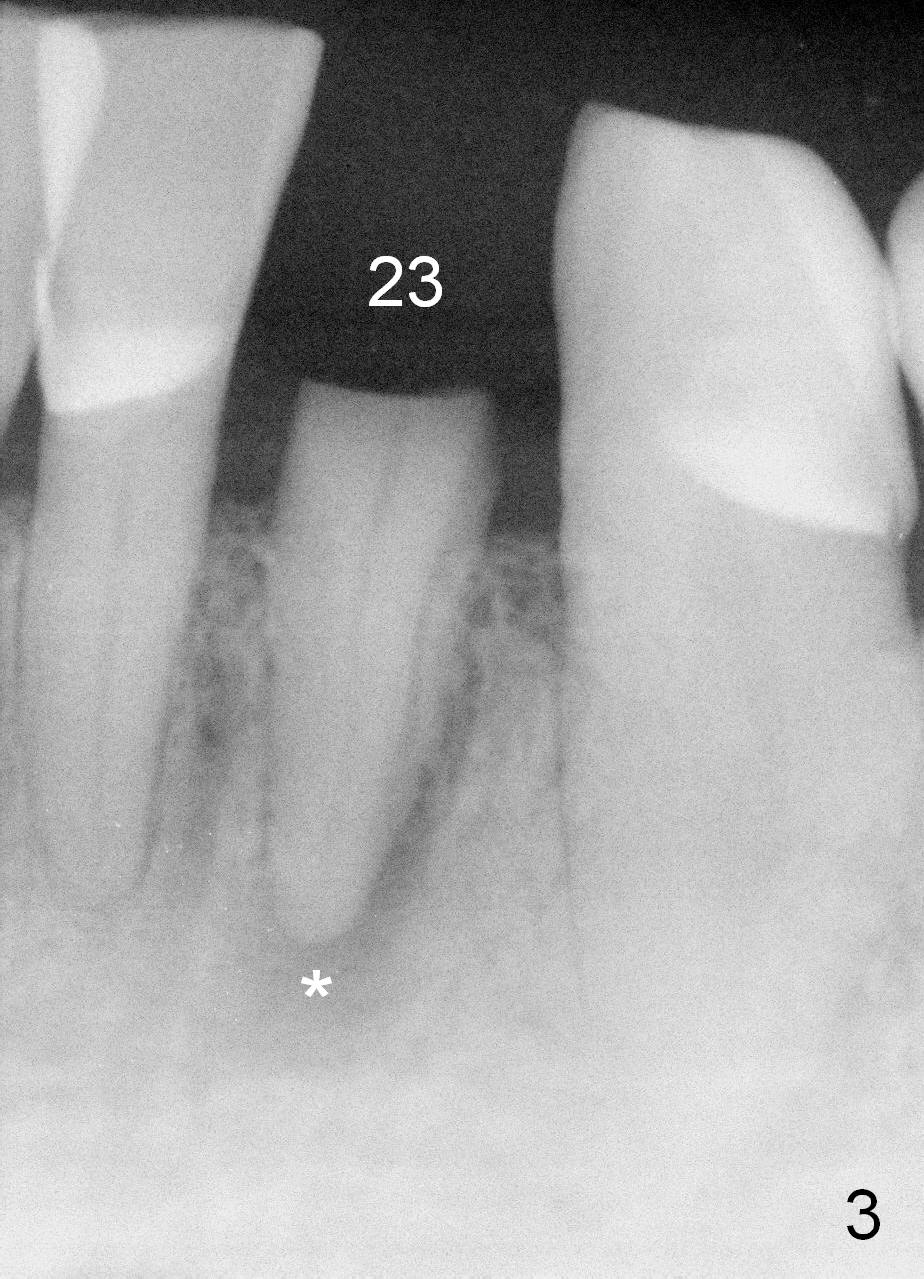

A 74-year-old man has several missing teeth (Fig.1).  His 1st goal is to replace the lower left lateral incisor (Fig.2).  The residual root has an apical lesion (Fig.3 *).  To describe intraop findings, a CT image of a different patient is used (Fig.4 coronal section; B: buccal; L: lingual).  After extraction, the buccal plate is found to be thin and low (Fig.5 arrowheads).  A 1.5 mm pilot drill (Fig.6 red line) is used to initiate osteotomy in the lingual plate of the socket.  Once the drill penetrates the lingual plate, the trajectory changes and the depth is 17 mm from the gingival margin (Fig.7).  A PA is taken (Fig.8); it appears that the osteotomy can be extended more apically.  When the pilot drill extends to 20 mm, there is sudden empty feeling.  The lingual plate has perforated (Fig.9).  A new osteotomy is established buccally (Fig.10 pink).  To avoid buccal plate perforation, especially in the buccal undercut area (>), the coronal end of the drill has to be tilted buccally (<--).  An angled abutment (3x20 mm, 15°) is placed (Fig.11,12).  The abutment is modified (Fig.13,14) to accommodate an immediate provisional (Fig.15,16 P).  Perio dressing is to be applied to prevent the bone graft from getting dislodged buccally (Fig.15).  The dressing is in place 7 days postop (Fig.17).